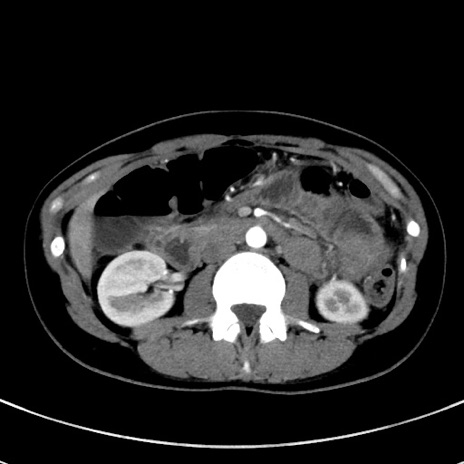

症例17(横断像)

【症例】20歳代女性

【主訴】嘔吐、下腹部痛

【現病歴】昨日夕食後に嘔吐し下腹部痛が出現。本日になっても嘔吐持続し改善しないため来院。

【身体所見】意識清明、BT 37.2℃、BP 108/67mmHg、腹部:平坦、やや硬、下腹部正中から右にかけて圧痛あり、反跳痛軽度あり、tapping pain(+)。

【データ】WBC 13600、CRP 14.94